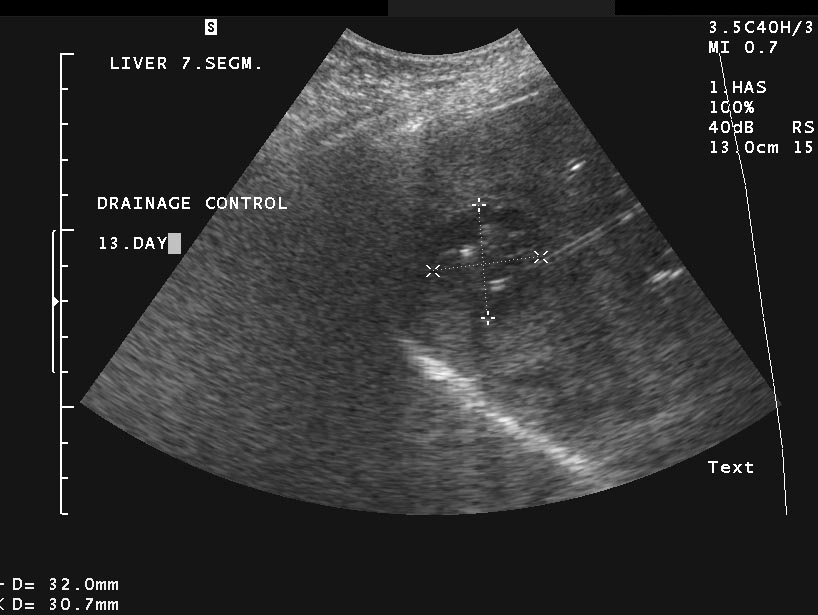

Liver abscess can develop either following the severe inflammation of the biliary ducts and the gallbladder or following a tumorous necrosis or by the spread of an external inflammation to the liver. By the help of the US, a cystic lesion can be seen with multiple internal echos containing gas bubble frequently as well. In order to determinate the further therapy, contrast enhanced CT examination can be needed, if the US imaging of the entire liver was not possible. An avascular intrahepatic lesion can be seen well on the CT with a contrast enhancing wall (sometimes multifocal as well) (Figure 30). An US or CT guided percutaneous drainage can provide a therapeutic result depending on the lesion's size and location (Figure 31).

Figure 30: Abscess in the liver, native CT

Figure 31: Abscess in the liver, US control after US guided drainage